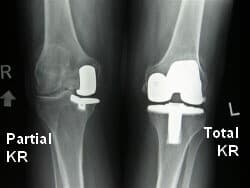

Зураг. Өвдөгний үе бүтэн болон дотор булууг хэсэгчлэн солих мэс засал.